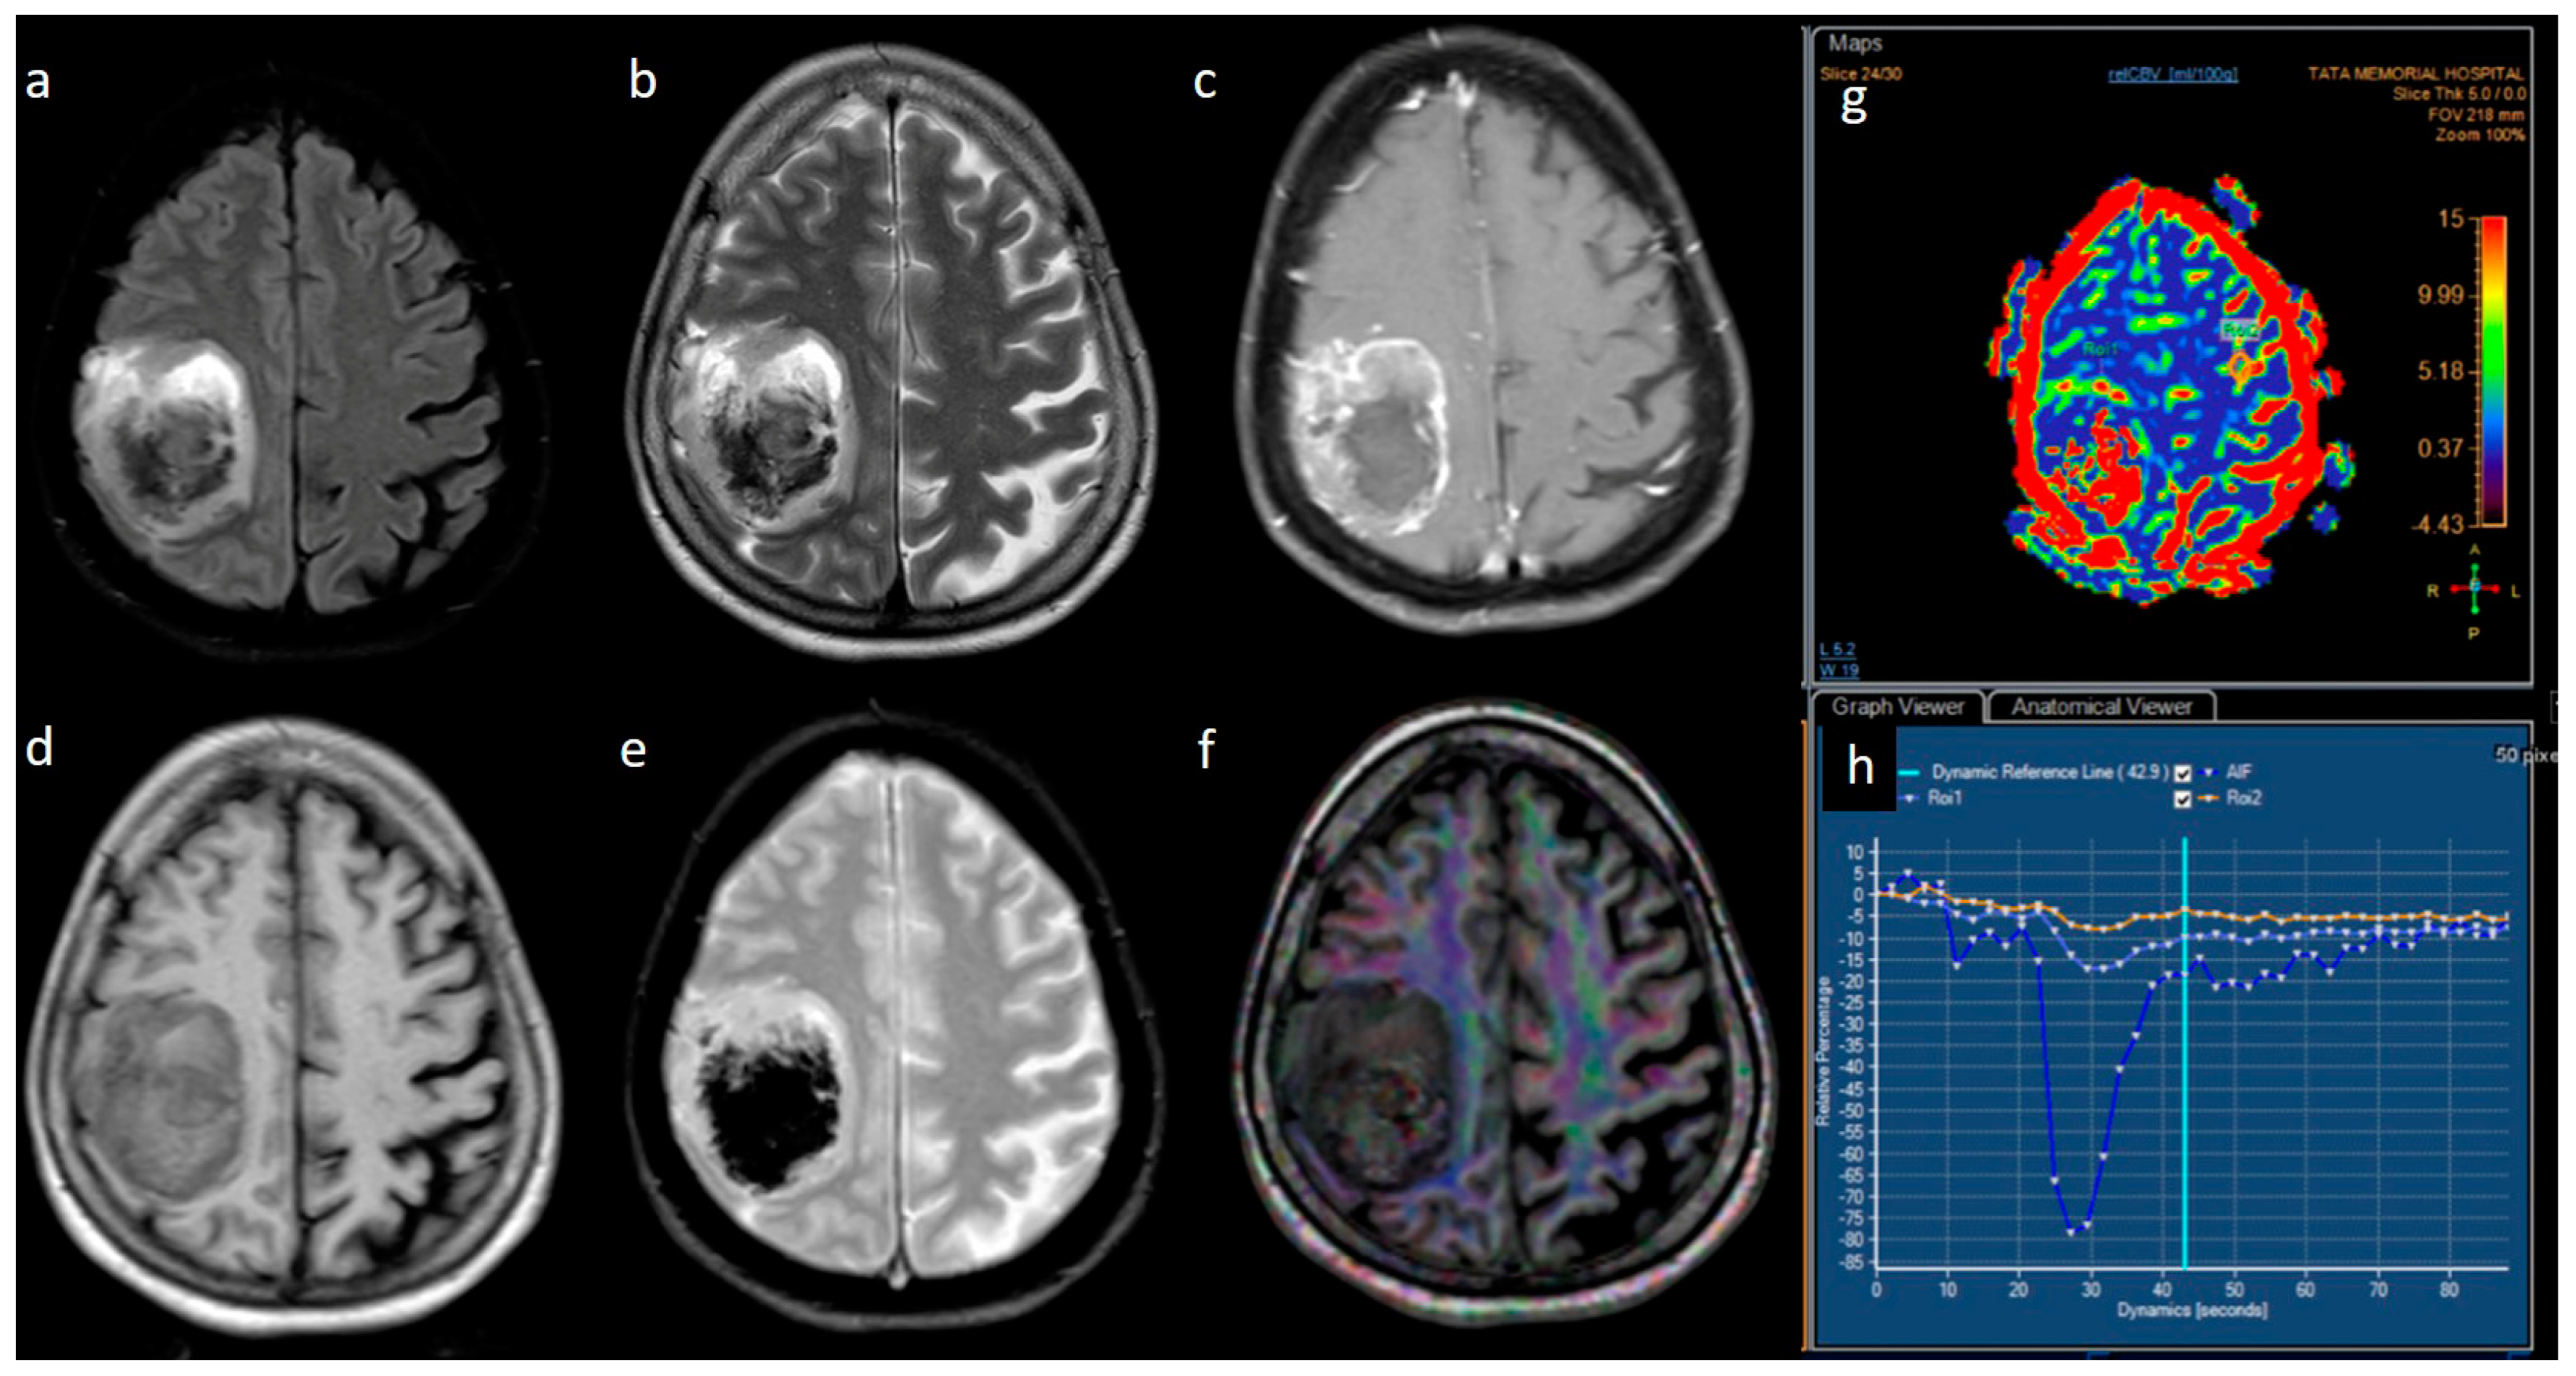

| rCBV | Median (IQR) | 1.8 [1.4–2.0] | 2.6 [1.9–3.5] | 0.001 |

| rCBV | <=2.0 | Reference | ||

| >2.0 | 0.12 | [0.03; 0.56] | 0.007 |